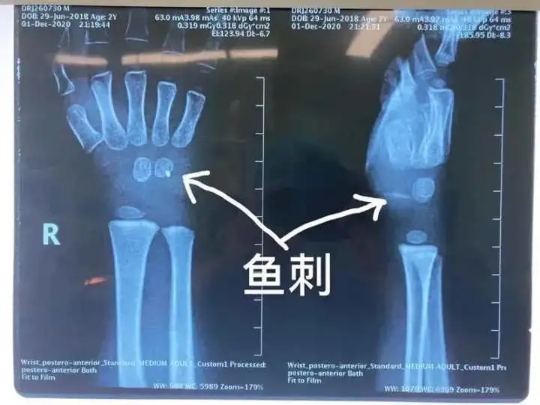

近日,杭州市兒童醫(yī)院骨科還接診了一名被魚刺扎傷手腕的小患者

原來,調(diào)皮的元元(化名)在家拿著魚玩耍,結(jié)果不小心忽然摔倒,魚刺深深地扎進了他的手腕。

醫(yī)生拍片檢查后發(fā)現(xiàn),魚刺已經(jīng)深及元元的手腕內(nèi)部約一厘米左右的位置。雖然體表傷口細小,但是內(nèi)部傷口附近神經(jīng)、血管交織錯雜,如不及時取出魚刺,會嚴重影響孩子的手腕功能。

手術(shù)室里,骨科醫(yī)生小心翼翼地取出魚刺后,再次探查周圍神經(jīng)、血管、肌腱,確定沒有殘留及其他損傷后,縫合傷口。經(jīng)過兩個多小時,終于為孩子解決這惱人的“不速之客”。